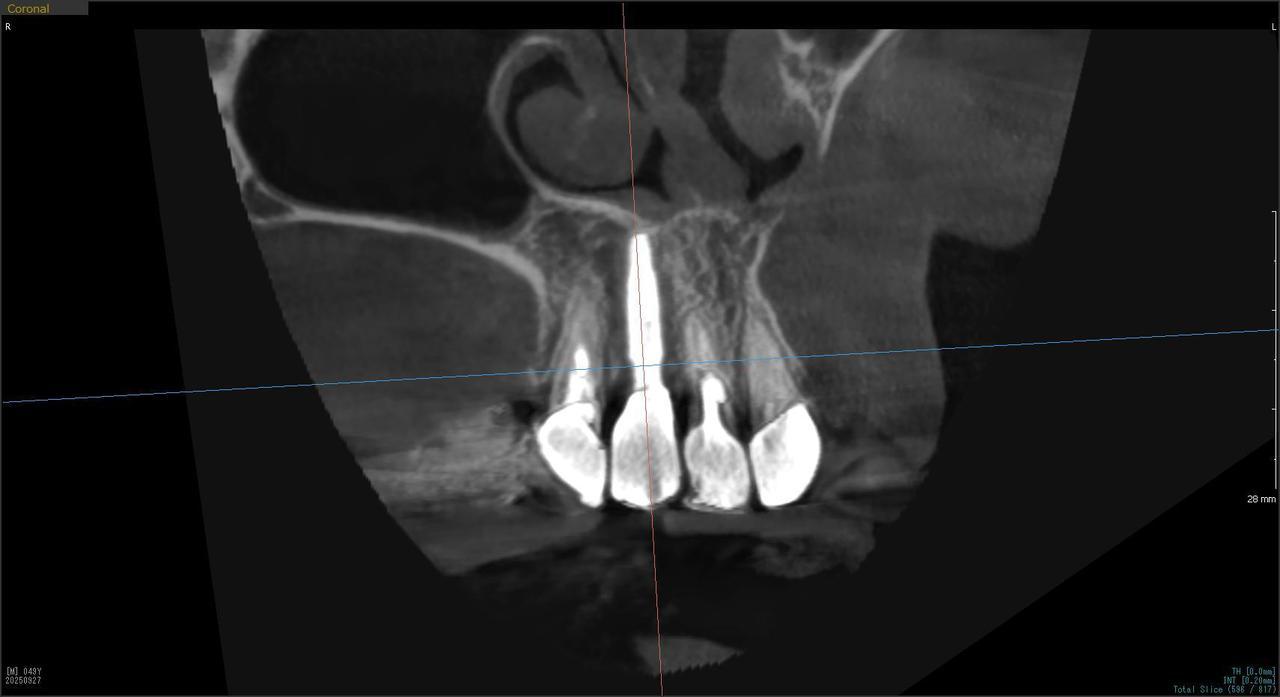

1.左上3番 インプラント抜歯即時埋入即時荷重(手術当日に抜歯を行い、当日に仮歯を入れています。)、左上4番 3ユニット式ブリッジが入るまでの暫間インプラントを埋入して当日に仮歯の装着。 左上5 既存骨3mmのグラフトレスサイナスリフト。最終補綴は、3ユニットジルコニアブリッジで治療を終えた症例

E・S様 女性 60代

患者様の症状としては、左上5番の排膿と重度の歯の動揺、重度の骨吸収、左上3番、中程度の骨吸収と中程度の歯の動揺、自発痛がありました。

治療法としては、左上3456にブリッジ治療が行われていたが、左上5の骨吸収と排膿を認めるために抜歯を行った2か月後に、患者様は、インプラント治療を希望。左上3の骨吸収と動揺も認めていたために、左上3を保存しても将来的な抜歯が予想されたため、左上3抜歯しての左上345の3ユニット式ブリッジ治療の計画を立てインプラント手術を行っています。患者様は、前歯がないことを気にされていたため、左上3番の抜歯と同時の仮歯製作と左上4番暫間インプラントにての仮歯製作を手術と同時に行っています。また、左上3番の歯肉退縮を予防するために、ご自分の歯の一部を温存するルートメンブレンテクニックを行っています。左上5に関しては、既存骨が3mm程度しかないので、グラフトレスサイナスリフトを施行して、表面の骨吸収した部分に骨補填材填入して、ボリュームを維持させていただいています。最終的な3ユニットブリッジは、ジルコニアで製作しています。補綴物の製作に関しては、オールデジタルで行っています。

治療結果は、患者様の希望通り、見えるところの歯がない状態なく、治療を終えることができたことと、また、グラフトレスサイナスリフトを施行することにより、従来のサイナスリフトを施行した場合と比較して、6時か月以上早く治療を終えることができたことと、ルートメンブレンテクニックを行うことで、歯肉退縮を少なくでき、自然な見た目で、最終補綴物を装着できました。従来のGBRやサイナスリフトを行わなかったことにより、短時間で、低侵襲に治療を終えることができ、審美面と機能面の回復を行うことができました。

治療の期間・回数:4か月、10回

治療の価格:814,000円(税込)

治療費の内訳:インプラント基本料(フィックスチャー及び手術費用、投薬費用、レントゲン費用、インプラント上部費用(アバットメントおよびジルコニアクラウンの費用用)右上3番5番 330000円×2 660000円(税込み)オプション費用 右上5グラフトレスサイナスリフト費用 33000円(税込み) 右上3抜歯即時荷重費用 33000円(税込み) 暫間インプラント費用 0円

治療のリスクや副作用:手術後に、痛みや腫れ、出血、合併症などを引き起こす可能性があります。噛む感覚がご自身の歯と異なる場合があります。見た目がご自身の歯と異なる場合があります。手術後にメインテナンスを継続しないと、インプラントが抜け落ちる可能性があります。